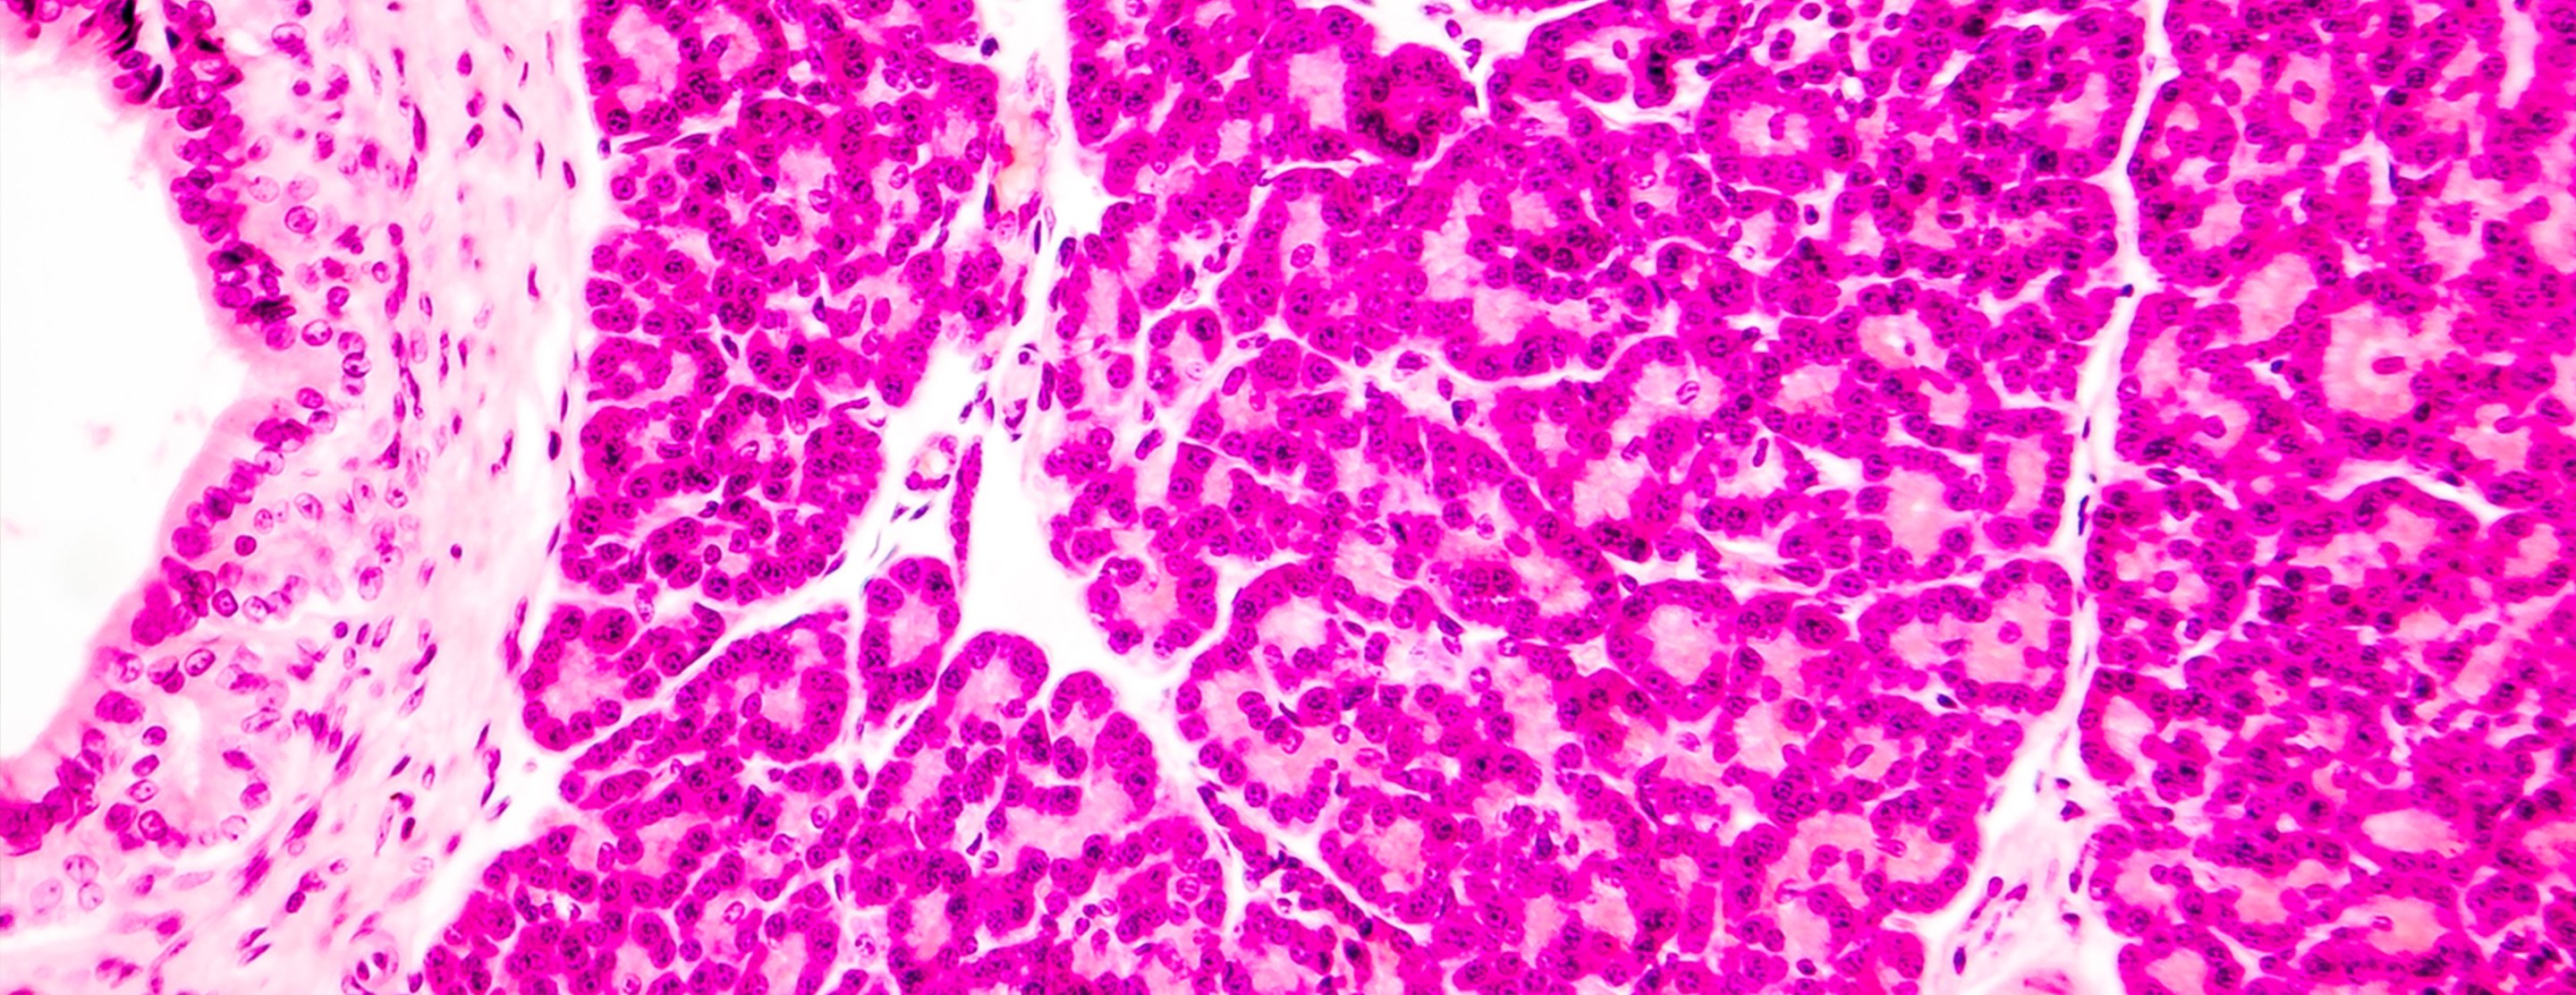

During an islet transplant for type 1 diabetes, insulin-producing beta cells – contained in clusters called islets – are isolated from a cadaver donor's pancreas, then injected through the skin into the portal vein of the recipient's liver. The islet cells flow into the liver, lodge in small blood vessels and release insulin.